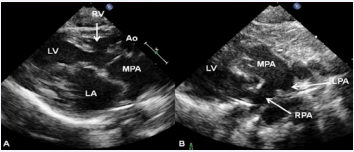

As mentioned in a preceding section (Table 1), tricuspid atresia is classified based on the relationship of the great arteries; the most common forms are: Type I, normally related great arteries, and Type II, d-transposition of the great arteries. The great artery relationship is established by following the vessel until bifurcation (Figure 8) or aortic arch. In babies with normally related great arteries the VSD provides blood flow into the lungs. In babies with associated transposition, the VSD provides systemic flow. The VSD may be small, causing obstruction to systemic flow and, therefore, the VSD size should be assessed by 2D (Figures 5, 7A, & 8A) and color (Figures 7B & 9), pulsed (Figure 10), and CW Doppler as necessary.

Figure 8 A) Selected video frame from parasternal long axis views of a neonate with tricuspid atresia and transposition of the great arteries demonstrating left atrium (LA), left ventricle (LV), a very small right ventricle (RV), and a moderate-sized ventricular septal defect (not marked). The vessel coming off of the LV is traced in B and shown to bifurcate into left (LPA) and right (RPA) pulmonary arteries, confirming that this vessel is the main pulmonary artery (MPA). Ao, Aorta [36].

Figure 8 A): Selected video frame from parasternal long axis views of a neonate with tricuspid atresia and transposition of the great arteries demonstrating left atrium (LA), left ventricle (LV), a very small right ventricle (RV), and a moderate-sized ventricular septal defect (not marked). The vessel coming off of the LV is traced in B and shown to bifurcate into left (LPA) and right (RPA) pulmonary arteries, confirming that this vessel is the main pulmonary artery (MPA). Ao, Aorta [36].